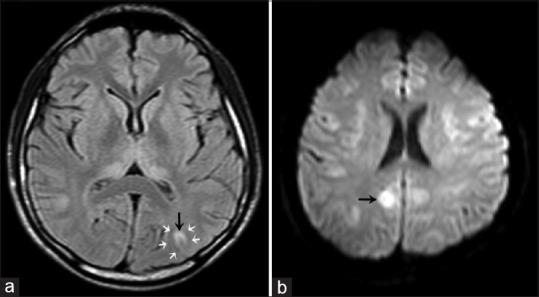

Butane is a commonly misused volatile agent, and a cause of intoxication. We present a case, who had a syncope and persistent ventricular fibrillation during the course of resuscitation. We discussed the management of this case in the intensive care unit and the accompanying difficulties in the light of the current literature.

https://cdn.ncbi.nlm.nih.gov/pmc/blobs/a49a/4563975/5f881098dea8/AER-9-273-g001.jpg